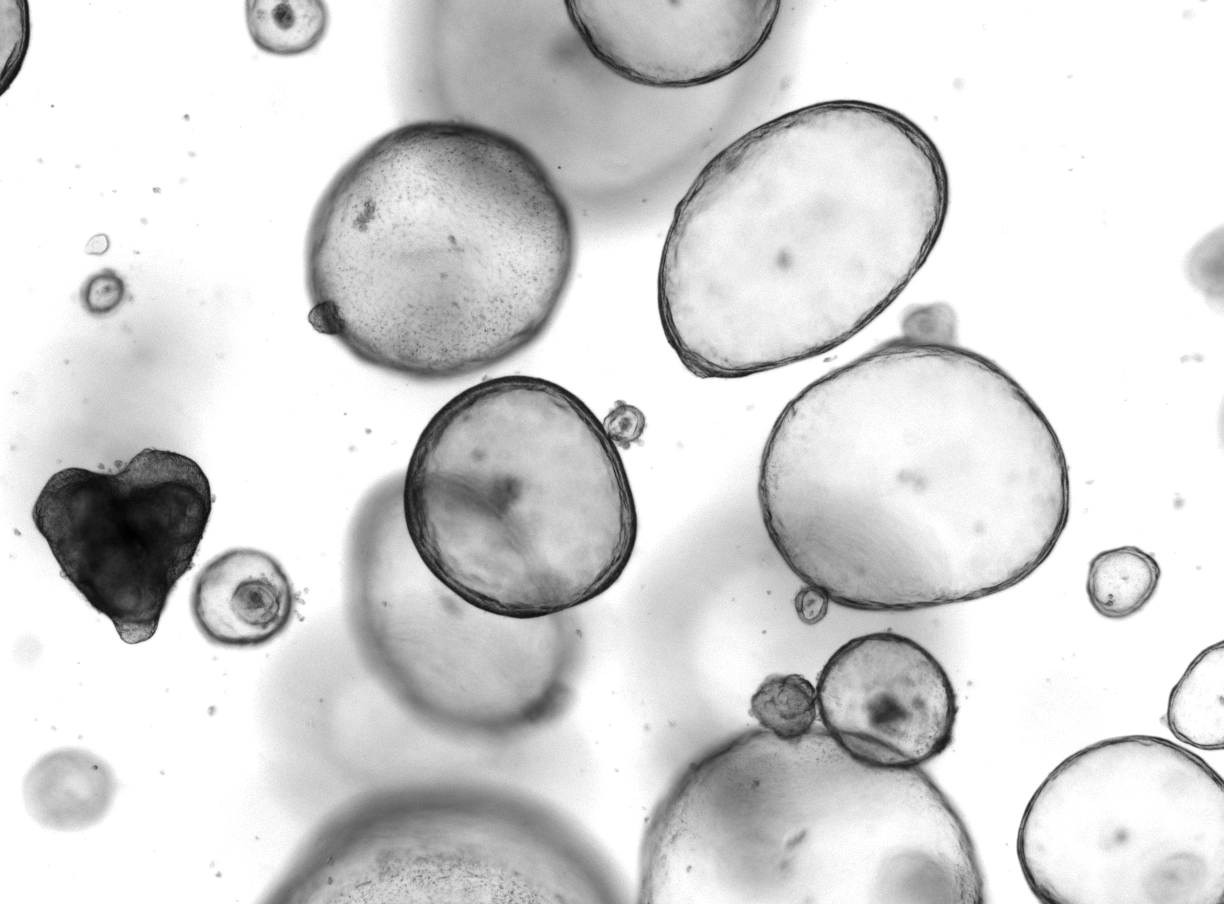

We established experimental platforms to mimic human tumors in laboratory settings. It is known that a tumor contains not only cancer cells, but entire microenvironment that is composed of the cellular and the non-cellular compartment. Therefore, we developed 3-dimensional heterotypic co-cultures that contain cancer cells, endothelial cells, fibroblasts, and selected immune cell subsets (Scientific Reports 2019; Cancers 2019, Cancers 2020). Together, these cells produce an extracellular matrix promoting the 3-dimensional structure formation. We use these co-cultures to (i) validate the anti-cancer efficacy of optimized multidrug combinations, (ii) characterize the selective targeting of cancer cells, (iii) monitor the behavior of the cells in response to the applied treatment, (iv) and more.

Foto by Mireia Carbo (FAMOL).